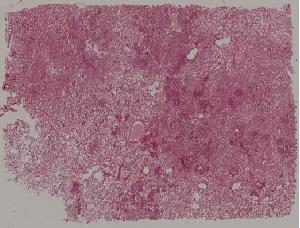

49.梅毒性主动脉炎

50.大叶性肺炎

51.肺肉质变

52.小叶性肺炎

57.肺癌

59.慢性萎缩性胃炎

60.胃溃疡

61.胃腺癌(胃粘液腺癌)

62.急性普通型病毒性肝炎

63.慢性活动性肝炎

64.急性重型病毒性肝炎

65.亚急性重型病毒性肝炎

66.活动性结节性肝硬化

67.非活动性结节性肝硬化

68.胆汁性肝硬化

69.肝细胞性肝癌

72.膜性肾小球肾炎

73.急性肾小球肾炎

74.新月体性肾炎

75.慢性硬化性肾小球肾炎